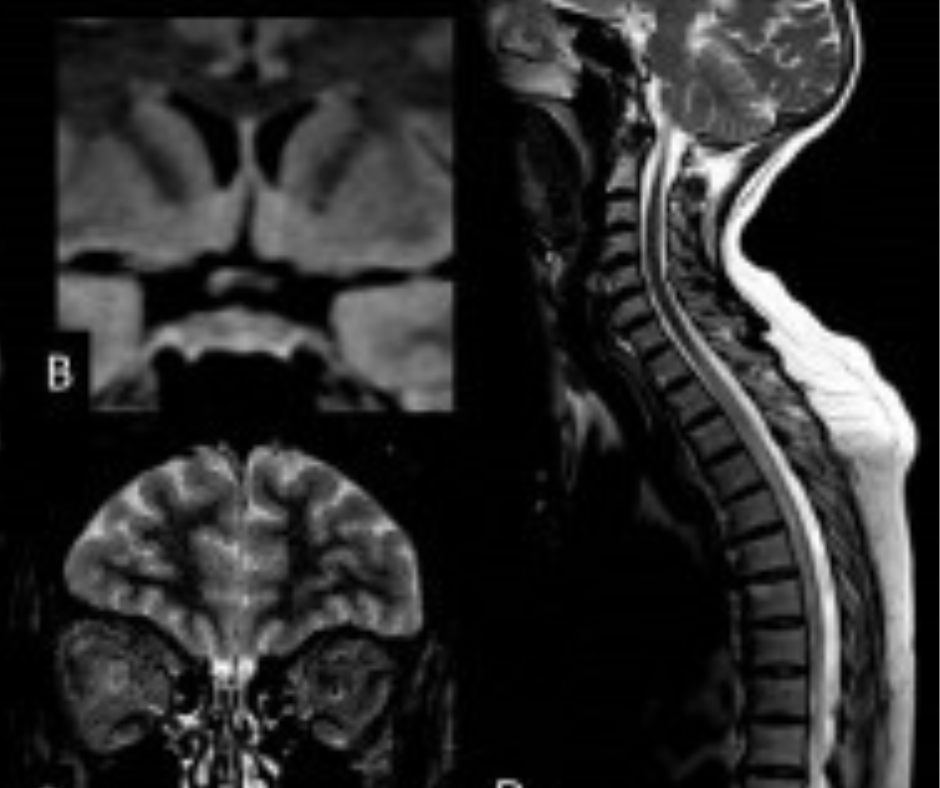

For neuromyelitis optica spectrum disorder (NMOSD), one would see mostly infratentorial lesions near the fourth ventricle. The linear, T2-hyperintense lesions may be contiguous with cervical transverse myelitis, according to the poster authors. They added that other key MRI findings include the appearance of diencephalic lesions in proximity to the third ventricle and rostral midbrain.

With Neuro-Behcet disease, Muga and colleagues said T2-weighted MRI will show edematous lesions that have a hyperintense appearance while one will note microhemorrhages on susceptibility-weighted imaging and contrast enhancement of acute lesions on T1-weighted MR images. Optic neuritis and intracranial sinus thrombosis are common with Neuro-Behcet diseases, according to the poster authors. Muga and colleagues also noted that infratentorial atrophy may result from chronic Neuro-Behcet disease.

When it comes to brain stem lesions caused by multiple sclerosis, Muga and colleagues said radiologists will see well-circumscribed, ovoid lesions that are found in the dorsal and ventral brain stem. More likely to occur in the pons than the medulla, these lesions are hyperintense on fluid-attenuated inversion recovery (FLAIR) sequences and T2-weighted MRI images, according to the poster authors.